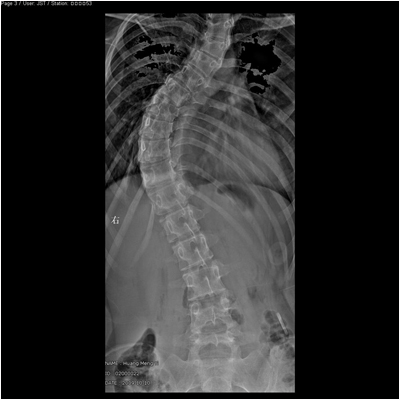

脊柱侧弯和后凸畸形病例一:女性,15岁,诊断:脊柱侧弯

术前正位平片